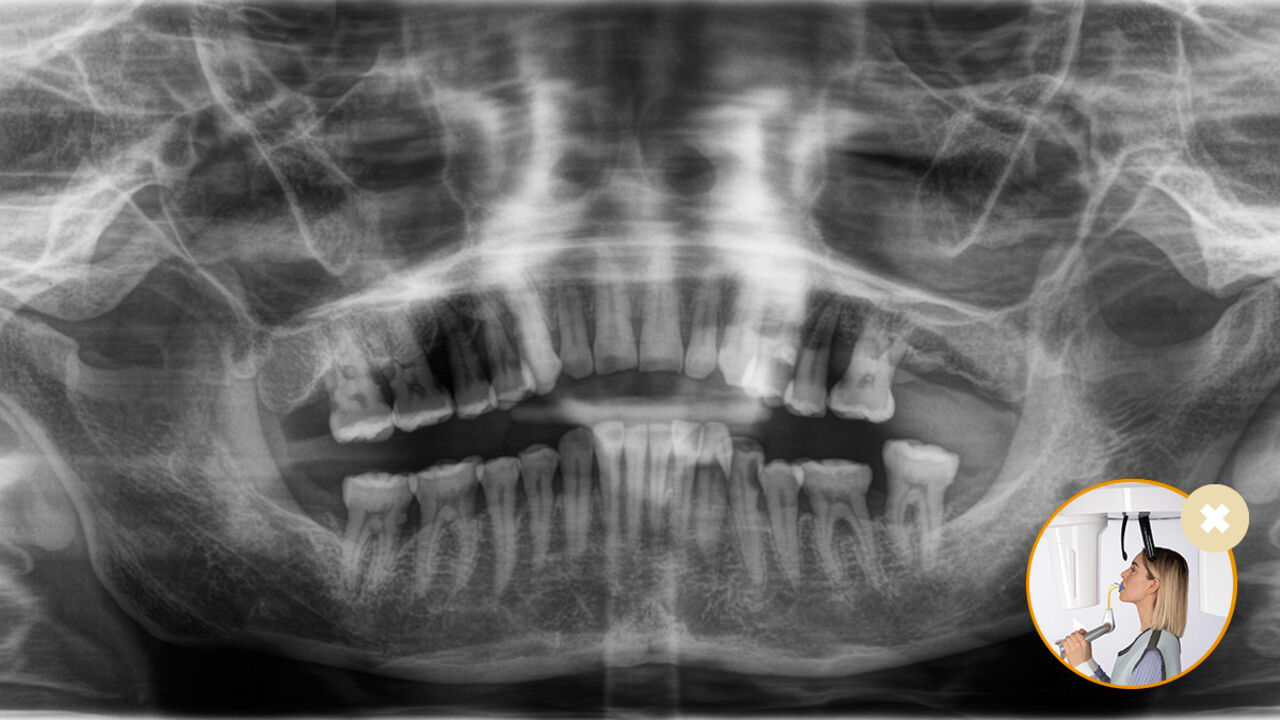

Ontspannen en aangename procedures zijn voor iedereen belangrijk, of het nu om patiënten gaat of het personeel. Het is voor iedereen fijn en motiverend als alles soepel en volgens plan verloopt. Met het gebruik van Orthophos of Axeos met Sidexis 4 krijgt u doelgerichte ondersteuning. De röntgensystemen zijn eenvoudig te gebruiken, maar bieden unieke diagnostische mogelijkheden. Dit waarborgt een positieve ervaring bij ieder aspect in het behandelingsproces.

Correcte patiëntpositionering leidt tot hoge beeldkwaliteit zodat een nauwkeurige diagnose wordt ondersteund en de patiëntervaring verbetert.

Dit is ons 10-puntenconcept voor een comfortabele patiëntpositionering en röntgenbeeldvorming. Het gaat primair om twee dingen: een hoge beeldkwaliteit en comfort voor zowel de patiënt als de assistent.